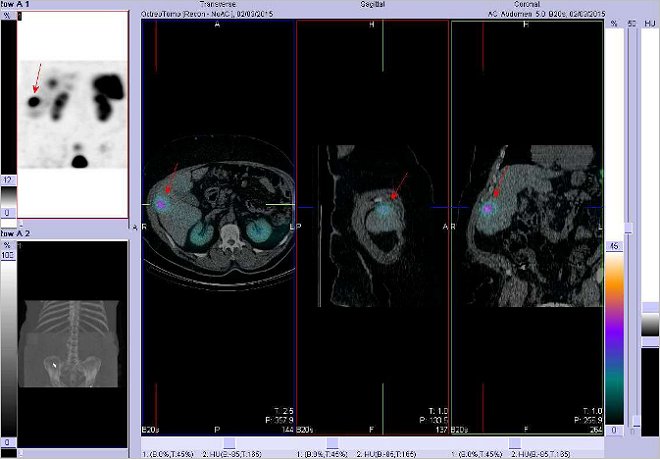

/ Obr.č.2: Fúze obrazů SPECT a CT. Zaměřeno na ložisko v pravém jaterním laloku. Řez transverzální, sagitální a koronární.

Vyšetření 4 hod. po aplikaci OctreoScanu. /